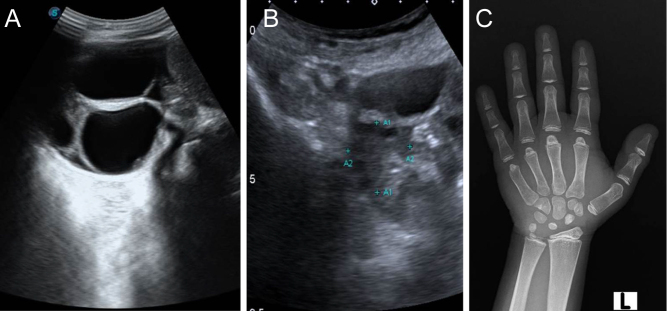

Summary: Ovarian hyperstimulation syndrome (OHSS) usually occurs in patients undergoing assisted reproduction techniques and ovulation induction. Its variant, spontaneous ovarian hyperstimulation syndrome, a potentially life-threatening disorder, is uncommon and only a few cases have been reported in association with hypothyroidism. This study analysed five patients with untreated chronic hypothyroidism presenting with multicystic ovaries, isosexual precocious puberty, and delayed bone age; subsequently, the follow-up and regression of ovarian pathology was assessed. Two patients had presented to the emergency department with menorrhagia and hypotension, of these, one had ovarian torsion at presentation. Three patients presented to the outpatient department: one for evaluation of short stature, one for premature menarche, and another with polycystic ovaries. They were all diagnosed with long-standing, untreated chronic hypothyroidism. There was regression of the size of the cystic ovaries on subsequent follow-up. In all these patients, long-standing hypothyroidism had resulted in ovarian hyperstimulation syndrome. The potentially life-threatening complications of this syndrome may be prevented by careful screening and a strong index of clinical suspicion at the outset.

Learning points: Long-standing, untreated primary hypothyroidism may result in spontaneous ovarian hyperstimulation syndrome. A high index of suspicion is required for an early and accurate diagnosis. The requirement for interdepartmental collaboration between gynaecology and endocrinology departments is essential for the successful management of this life-threatening but easily treatable disorder.